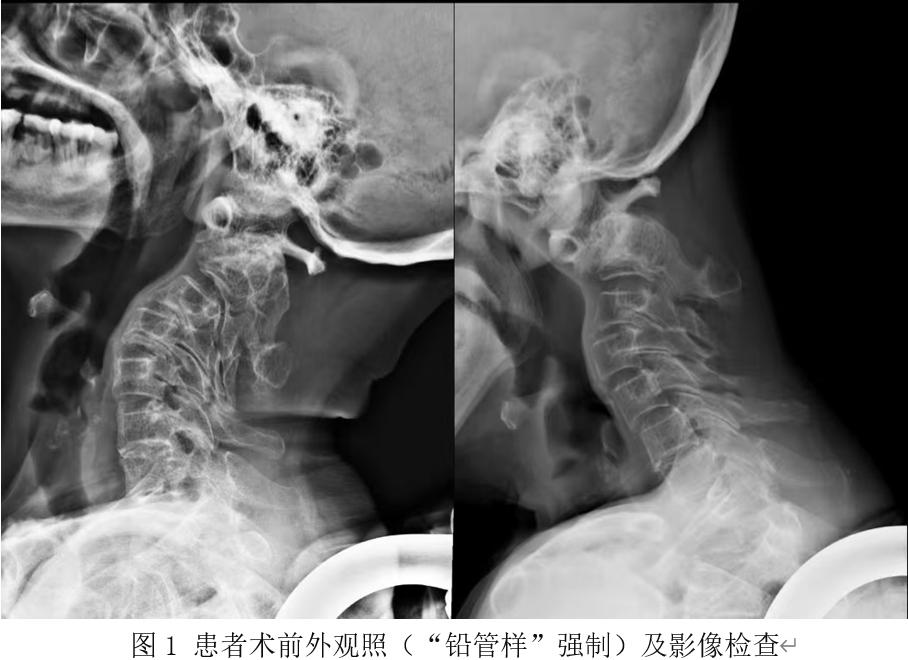

患者王女士(化名),71岁,因“四肢无力伴关节僵硬1月余”入院。入院时,患者已无法站立行走,处于长期卧床状态,并伴有小便排出障碍。影像检查显示,其寰枢关节脱位形成“枷锁”样结构,严重压迫颅颈交界段脊髓并导致变性。术前患者四肢感觉减退,肌张力增高呈“铅管样”强直,四肢肌力明显下降,右上肢仅可见肌肉收缩,无法活动(肌力1级)。